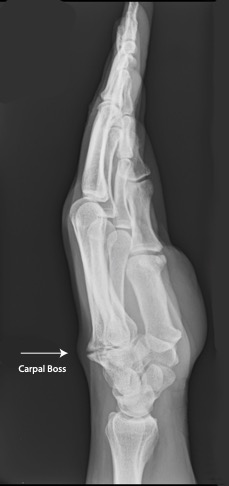

The diagnosis of a carpal boss is made on clinical examination. X-rays and sometimes a CT or MRI scan may be performed to confirm the diagnosis.